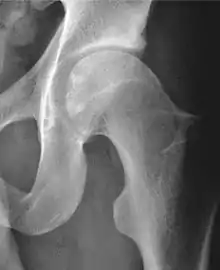

Projectional radiography ("X-ray")is often considered first line for FAI.[10] Anterior-posterior pelvis and a lateral image of the hip in question should be attained.[10] A 45-degree Dunn view is also recommended.[10][19]